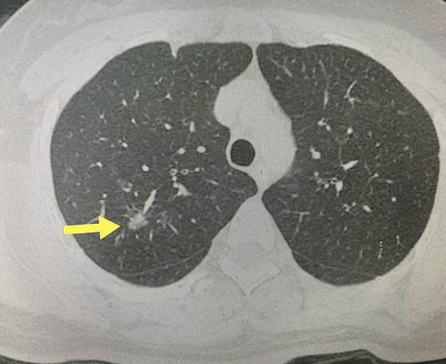

磨玻璃结节是不是早期肺癌?它有什么特点?

1、绝大多数的磨玻璃结节是良性的比如说炎症、肺的纤维化、肺内的小的微细血管的出血等等,都会引起磨玻璃样的改变。

2、即使是肿瘤,即使跟肿瘤相关,磨玻璃结节也是肿瘤的早期中的早期状态或者叫做前期状态。我们医学上称作腺体前驱病变,就是癌前病变。可能3年5年10年8年它都不会生长,因此它不影响我们的健康,不影响我们的生命